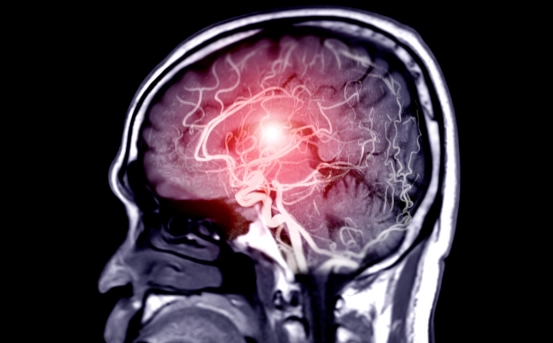

What is Epidural Hematoma Surgery?

Epidural Hematoma Surgery is performed to remove blood pooled between the skull and the outer layer of the brain, known as the dura mater. This condition usually occurs due to trauma, accidents, or skull fractures and leads to rapid pressure buildup. The surgery prevents brain damage, restores blood flow, and stabilizes the patient. Early intervention is critical for successful recovery.